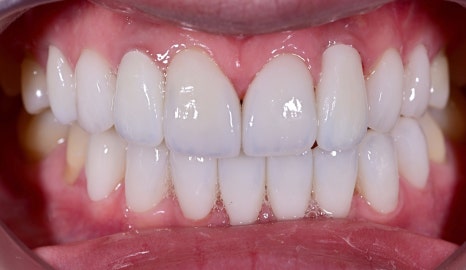

안녕하세요, 오브치과입니다. 라미네이트와 임플란트를 동시에 시술할 수 있다는 사실을 알고 계셨나요? 어떤 게 임플란트일까요? 오늘 소개해드릴 증례는 기존 앞니 임플란트의 부자연스러운 느낌을 개선하고 싶어 내원하신 환자분으로 오브제로 라미네이트와 임플란트 보철 치료를 함께 진행하여 보다 자연스럽고 아름답고 빛나는 미소를...

어떤 게 임플란트일까요?

오늘 소개해드릴 증례는 기존 앞니 임플란트의 부자연스러운 느낌을 개선하고 싶어 내원하신 환자분으로

오브제로 라미네이트와 임플란트 보철 치료를 함께 진행하여 보다 자연스럽고 아름답고 빛나는 미소를 완성한 케이스입니다.

치료 후 변화

치료 후 가장 큰 변화는 “더 이상 임플란트가 따로 놀지 않는다”는 점이었습니다.

기존에는 임플란트 부위가 주변 치아와 미묘하게 다르게 보여 앞니 전체의 통일감을 해치고 있었지만, 치료 후에는 앞니의 색감과 형태, 비율이 훨씬 부드럽게 연결되면서 전체 인상이 한층 정돈되고 자연스러워졌습니다.

또한 너무 차갑거나 인위적인 흰색이 아니라 환자분 이미지에 어울리는 깨끗하고 고급스러운 화이트 톤으로 완성되어 웃을 때의 분위기 자체가 훨씬 밝아졌습니다.